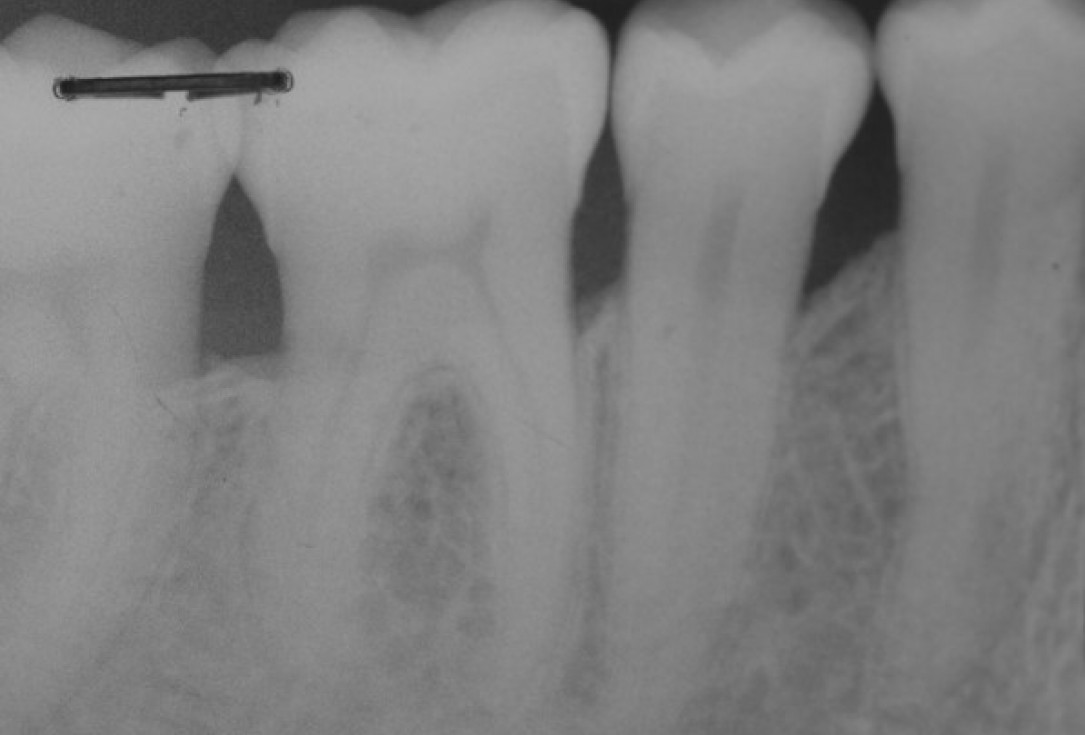

Radiographic view before periodontal regenerative therapy with Straumann® Emdogain®. A deep intrabony defect appeared mesially and distally on the left mandibular first premolar. Pre-surgical probing measured 8 mm. The defect morphology presented as well-contained.